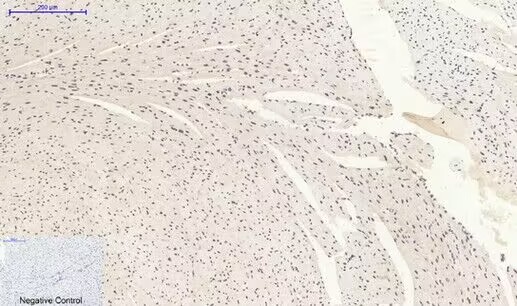

Immunohistochemical analysis of paraffin-embedded Mouse-heart tissue.